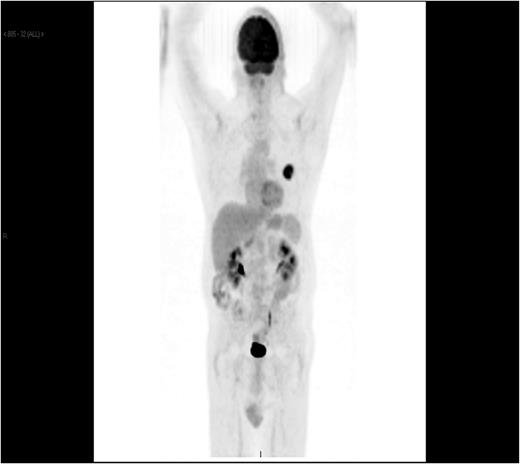

A 61-year-old male presented with a 2-week history of worsening posterior neck and bilateral shoulder pain, and a several hour history of severe, left-sided abdominal tenderness. The patient reported no recent history of trauma. The patient had been diagnosed with poorly differentiated, left lung adenocarcinoma 5 months prior; he was status-post left upper lobectomy. PET scan, at that time (Fig. 1), showed no evidence of metastatic disease and the pathologic staging was determined to be T2aN0M0 (Stage 1B).

PET CT showing left lingular malignancy and no evidence of metastasis.